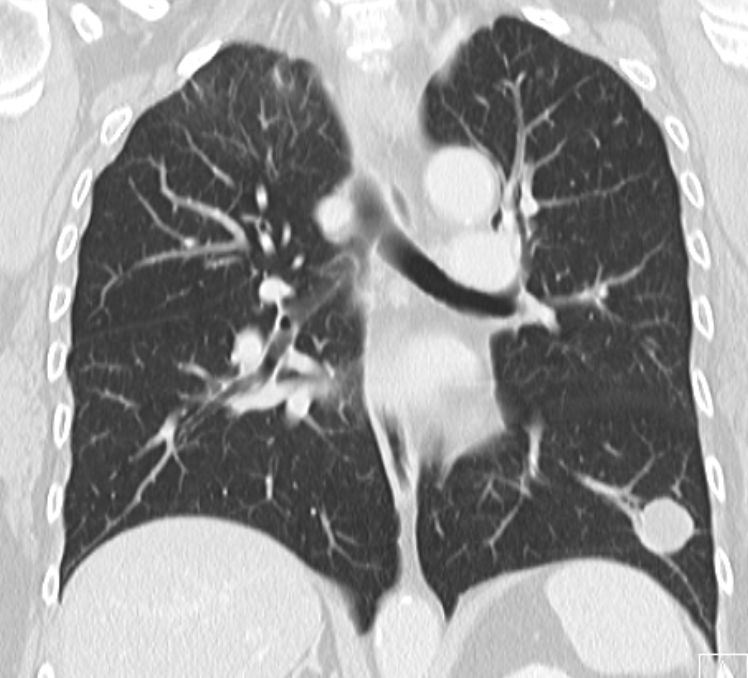

67-jährige Frau vor 2 Jahren Mammakarzinom pT1a

pN1a Mo L1 und Nierenzellkarzinom. Vor 4 Monaten Lungenmetastasen. Partielle

Remission unter Pazopanib.![]() | ||||